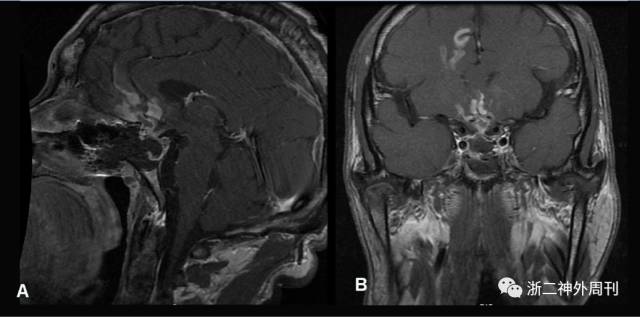

术后情况:患者术后一般情况可,神清语利,术后继续口服补充皮质醇及甲状腺激素,术后第二天复查生长激素0.68ng/mL、IGF-1 224.0ng/mL、IGFBP-3 2.79μg/mL↓、皮质醇(8am)134.5nmol/L↓。术后复查垂体增强MR提示减压充分,肿瘤次全切除(图7)。患者术后无尿崩,无发热,无脑脊液漏等并发症,血糖控制可,于2017年6月6日出院,转当地医院继续治疗,嘱患者神经外科,内分泌科,心内科门诊随访。

图7. 术后复查MRI矢状位(A)与冠状位(B)提示肿瘤次全切除术,垂体柄居中。